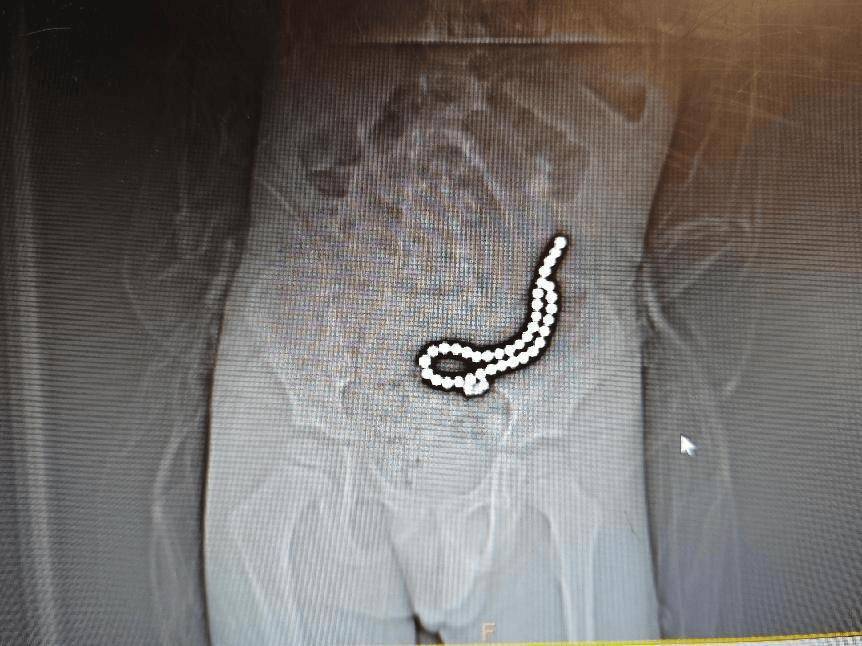

磁力珠色彩绚丽、玩法多样,深受小朋友喜爱。但如果误食,后果却会很严重。 近日,丽江市人民医院接收了一名因误吞磁力珠而生命垂危的小儿患者。这名4岁的孩子,在家中玩...